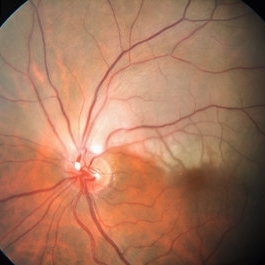

Retina Images (13 files)

Retina Images (13 files)